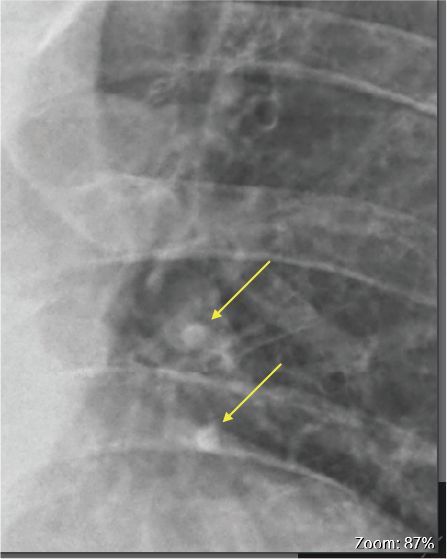

1.兩肺纖維化

2.左肺門附近結節x2,約0.4公分

3.血氧濃度92%